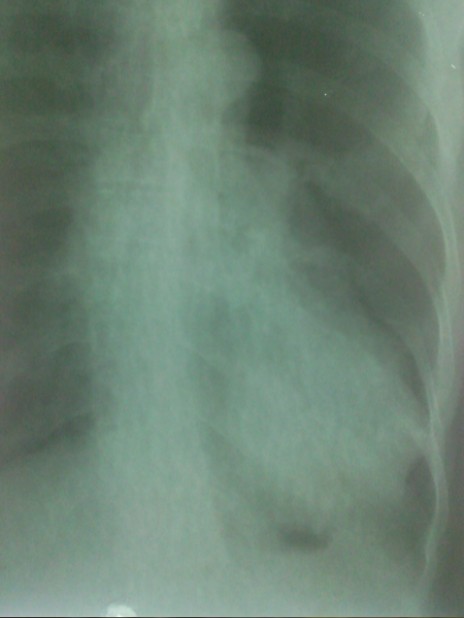

患者男,50岁,反复咳嗽、咳痰10余年,加重并气促3天。

片子质量不好,肺气肿肺心病

侧位,纵膈内病灶?

建议加照侧位,或ct检查除外左下肺或纵膈病变。

左下胸膜肥厚?

建议加照侧位,或ct检查除外左下肺或纵膈病变

慢支、肺气肿,左下肺感染,肺心?